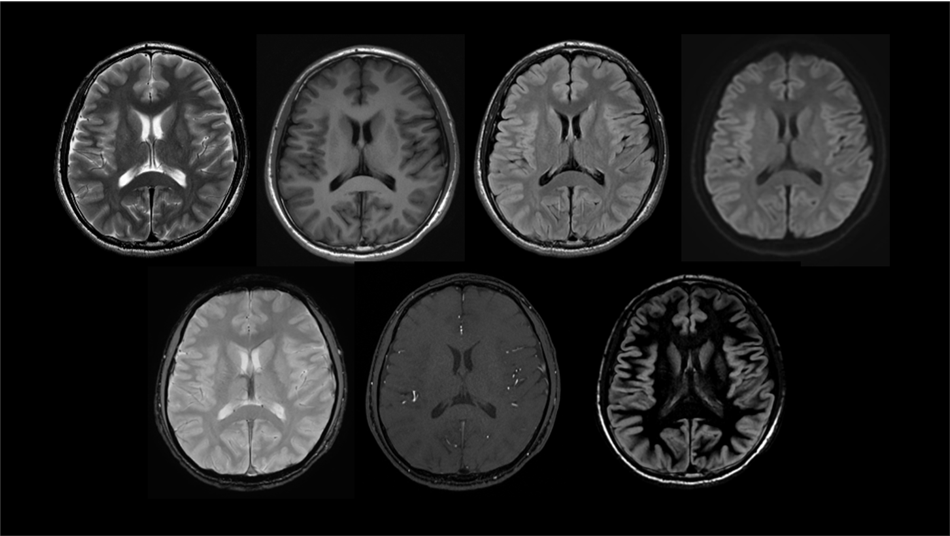

頭部画像

血管画像(MRA)